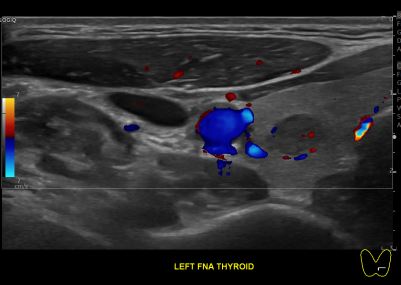

상기환자 외부건진 갑상선 이상소견으로 세침검사위해 내원하신 50대 초반 여성분으로

의심스러운 갑상선 좌엽 세포검사후 갑상선암으로 진단되었습니다